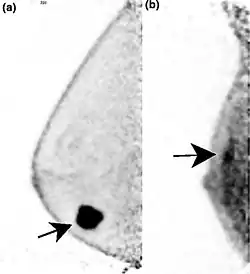

![]() Two PEM images, including sites of tracer uptake | |